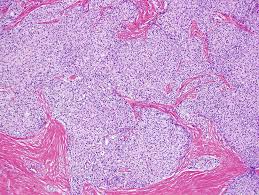

Papillary Thyroid Cancer | Prostate cancer is a common type of cancer in men, according to the mayo clinic. These include your blood pressure, heart rate and metab. If you have been diagnosed with adenocarcinoma cancer, you have a cancer that developed in one of the glands that lines the inside of your organs. It may grow slowly and it's typically treatable. Adenocarcinoma cancers being usually in one of the following organs:

Papillary Thyroid Cancer: The pancreas is an organ that releases enzymes involved with digestion, and hormones to regular blood sugar levels.